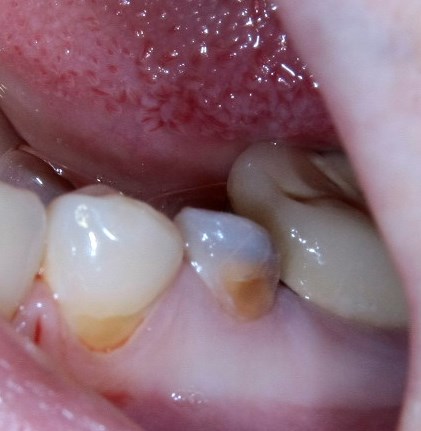

Немедленная имплантация — оптимальное решение в любой клинической ситуации